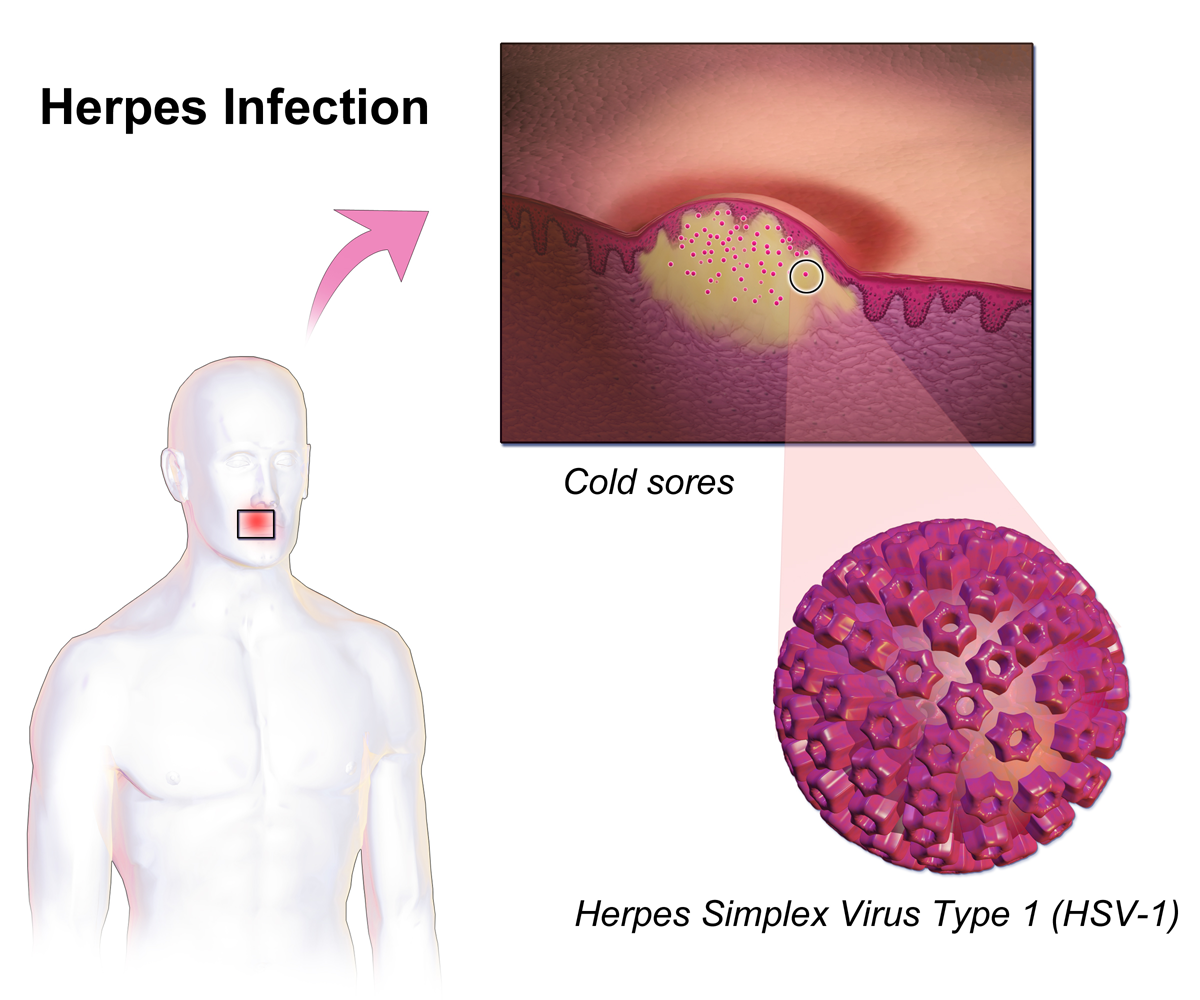

Медицинские снимки и изображения опоясывающего герпес вируса